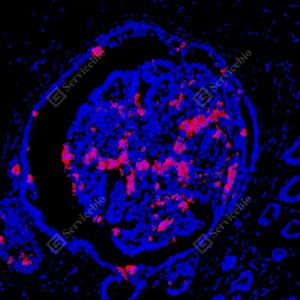

| IF检测Mammaglobin A蛋白(货号 GB15106)(红色). 样品: 人乳腺癌, 4%多聚甲醛 (货号G1101) 固定12-24小时. 抗原修复: Tris-EDTA抗原修复液(pH 9.0) (G1203), 98℃, 20分钟. 封闭: 3% BSA(货号GC305010)的PBS溶液, 室温孵育30分钟. —抗: 1: 1000稀释, 4℃ 孵育过夜. 二抗: Cy3标记山羊抗小鼠IgG (H+L) (货号GB21301), 1: 300稀释, 室温孵育1小时. |